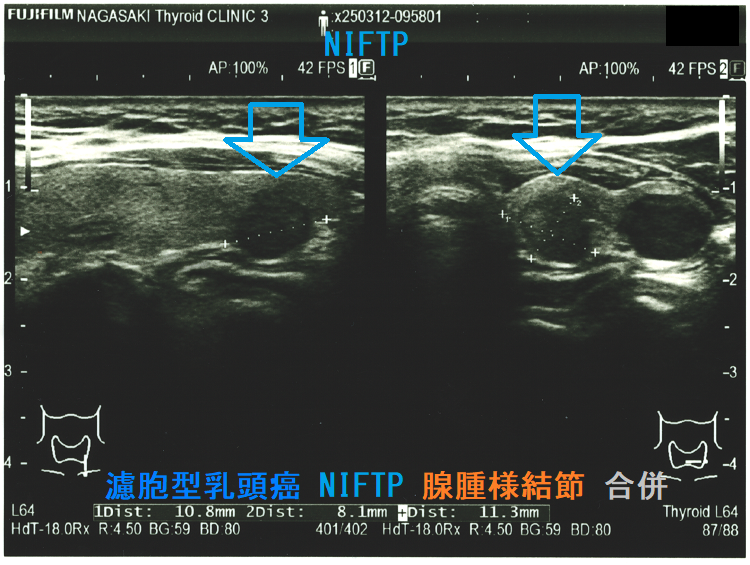

Non-invasive follicular thyroid neoplasm with papillary-like nuclear features (NIFTP) 超音波(エコー)画像;見かけは濾胞型甲状腺乳頭癌、濾胞性腫瘍と鑑別できまない

(a)Non-invasive follicular thyroid neoplasm with papillary-like nuclear features (NIFTP) 超音波(エコー)画像;見かけは濾胞型甲状腺乳頭癌、甲状腺濾胞癌、腺腫様結節と鑑別できまない

Non-invasive follicular thyroid neoplasm with papillary-like nuclear features (NIFTP)の超音波(エコー)所見は、

- 被膜が存在(被膜のない場合もある)

- 充実性、等エコーが多い

- 砂粒状石灰化を認めない

などで、濾胞型甲状腺乳頭癌、濾胞性腫瘍(良性濾胞腺腫 、甲状腺濾胞癌)と鑑別できません。砂粒状石灰化のない濾胞型甲状腺乳頭癌なんて普通に存在します。NIFTPの60.1%は悪性を疑う所見が無いとされます[Endocrine. 2021 Jul;73(1):131-140.]。